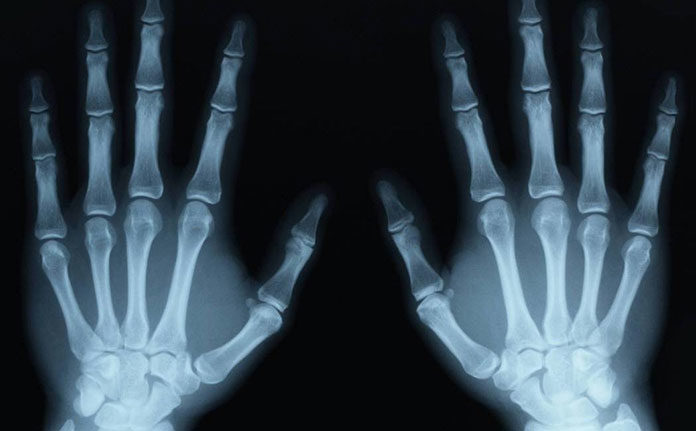

Badanie rentgenowskie jest powszechnym badaniem obrazowym, które jest stosowane od dziesięcioleci. Może pomóc lekarzowi zobaczyć wnętrze twojego ciała bez konieczności wykonywania nacięcia. Może to pomóc zdiagnozować, monitorować i leczyć wiele schorzeń.

Różne rodzaje promieni rentgenowskich są wykorzystywane do różnych celów. Na przykład lekarz może zlecić badanie mammograficzne piersi. Lub mogą zamówić zdjęcie rentgenowskie z lewatywą barową, aby przyjrzeć się bliżej układowi przewodu pokarmowego.

Warunki, które mogą wymagać prześwietlenia obejmują:

- złamania,

- artretyzm,